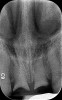

A 29-year-old Caucasian woman presented to the author's (GAM) practice for evaluation of teeth Nos. 8 and 9. The teeth were fractured at the free gingival margin and had sclerosed dental pulps (Figure 7 and Figure 8). The patient's medical history was significant for gastroesophageal reflux disorder (GERD), migraines, narcolepsy, attention deficit hyperactivity disorder (ADHD), and depression. She had no known drug allergies or drug idiosyncrasies and was determined to have an American Society of Anesthesiologists (ASA) II physical status.

A comprehensive periodontal examination was performed. A thermoplastic retainer and arm were fabricated for the patient with the fiduciary marker (CT marker) attached to the fix plate. Great care was taken regarding the fit of the thermoplastic stent to ensure proper seating. A CBCT scan (CS 9300, Carestream Dental, carestreamdental.com) of the maxilla was secured, and the DICOM data were registered into the planning software.

The surgery was performed under local-regional anesthesia. The thermoplastic retainer was placed over the remaining teeth and its fit/stability verified. Atraumatic extractions of teeth Nos. 8 and 9 were performed, and intact buccal bone was verified. Osteotomy site preparation and immediate implant placement were performed using the dynamic surgical navigation system. Two 3.6 mm x 9 mm implant fixtures (Astra Tech EV, Dentsply Sirona, dentsplysirona.com) were placed. SmartPegs (Osstell, osstell.com) were attached to the implants to show the trajectory of the fixture positioning. After implant placement, anorganic bovine bone matrix (Bio-Oss®, Geistlich Pharma, geistlich-na.com) was used to graft the implant alveolus "gap," and healing abutments were placed (Figure 9 and Figure 10). The patient was provided with an interim removable appliance for tooth replacement.